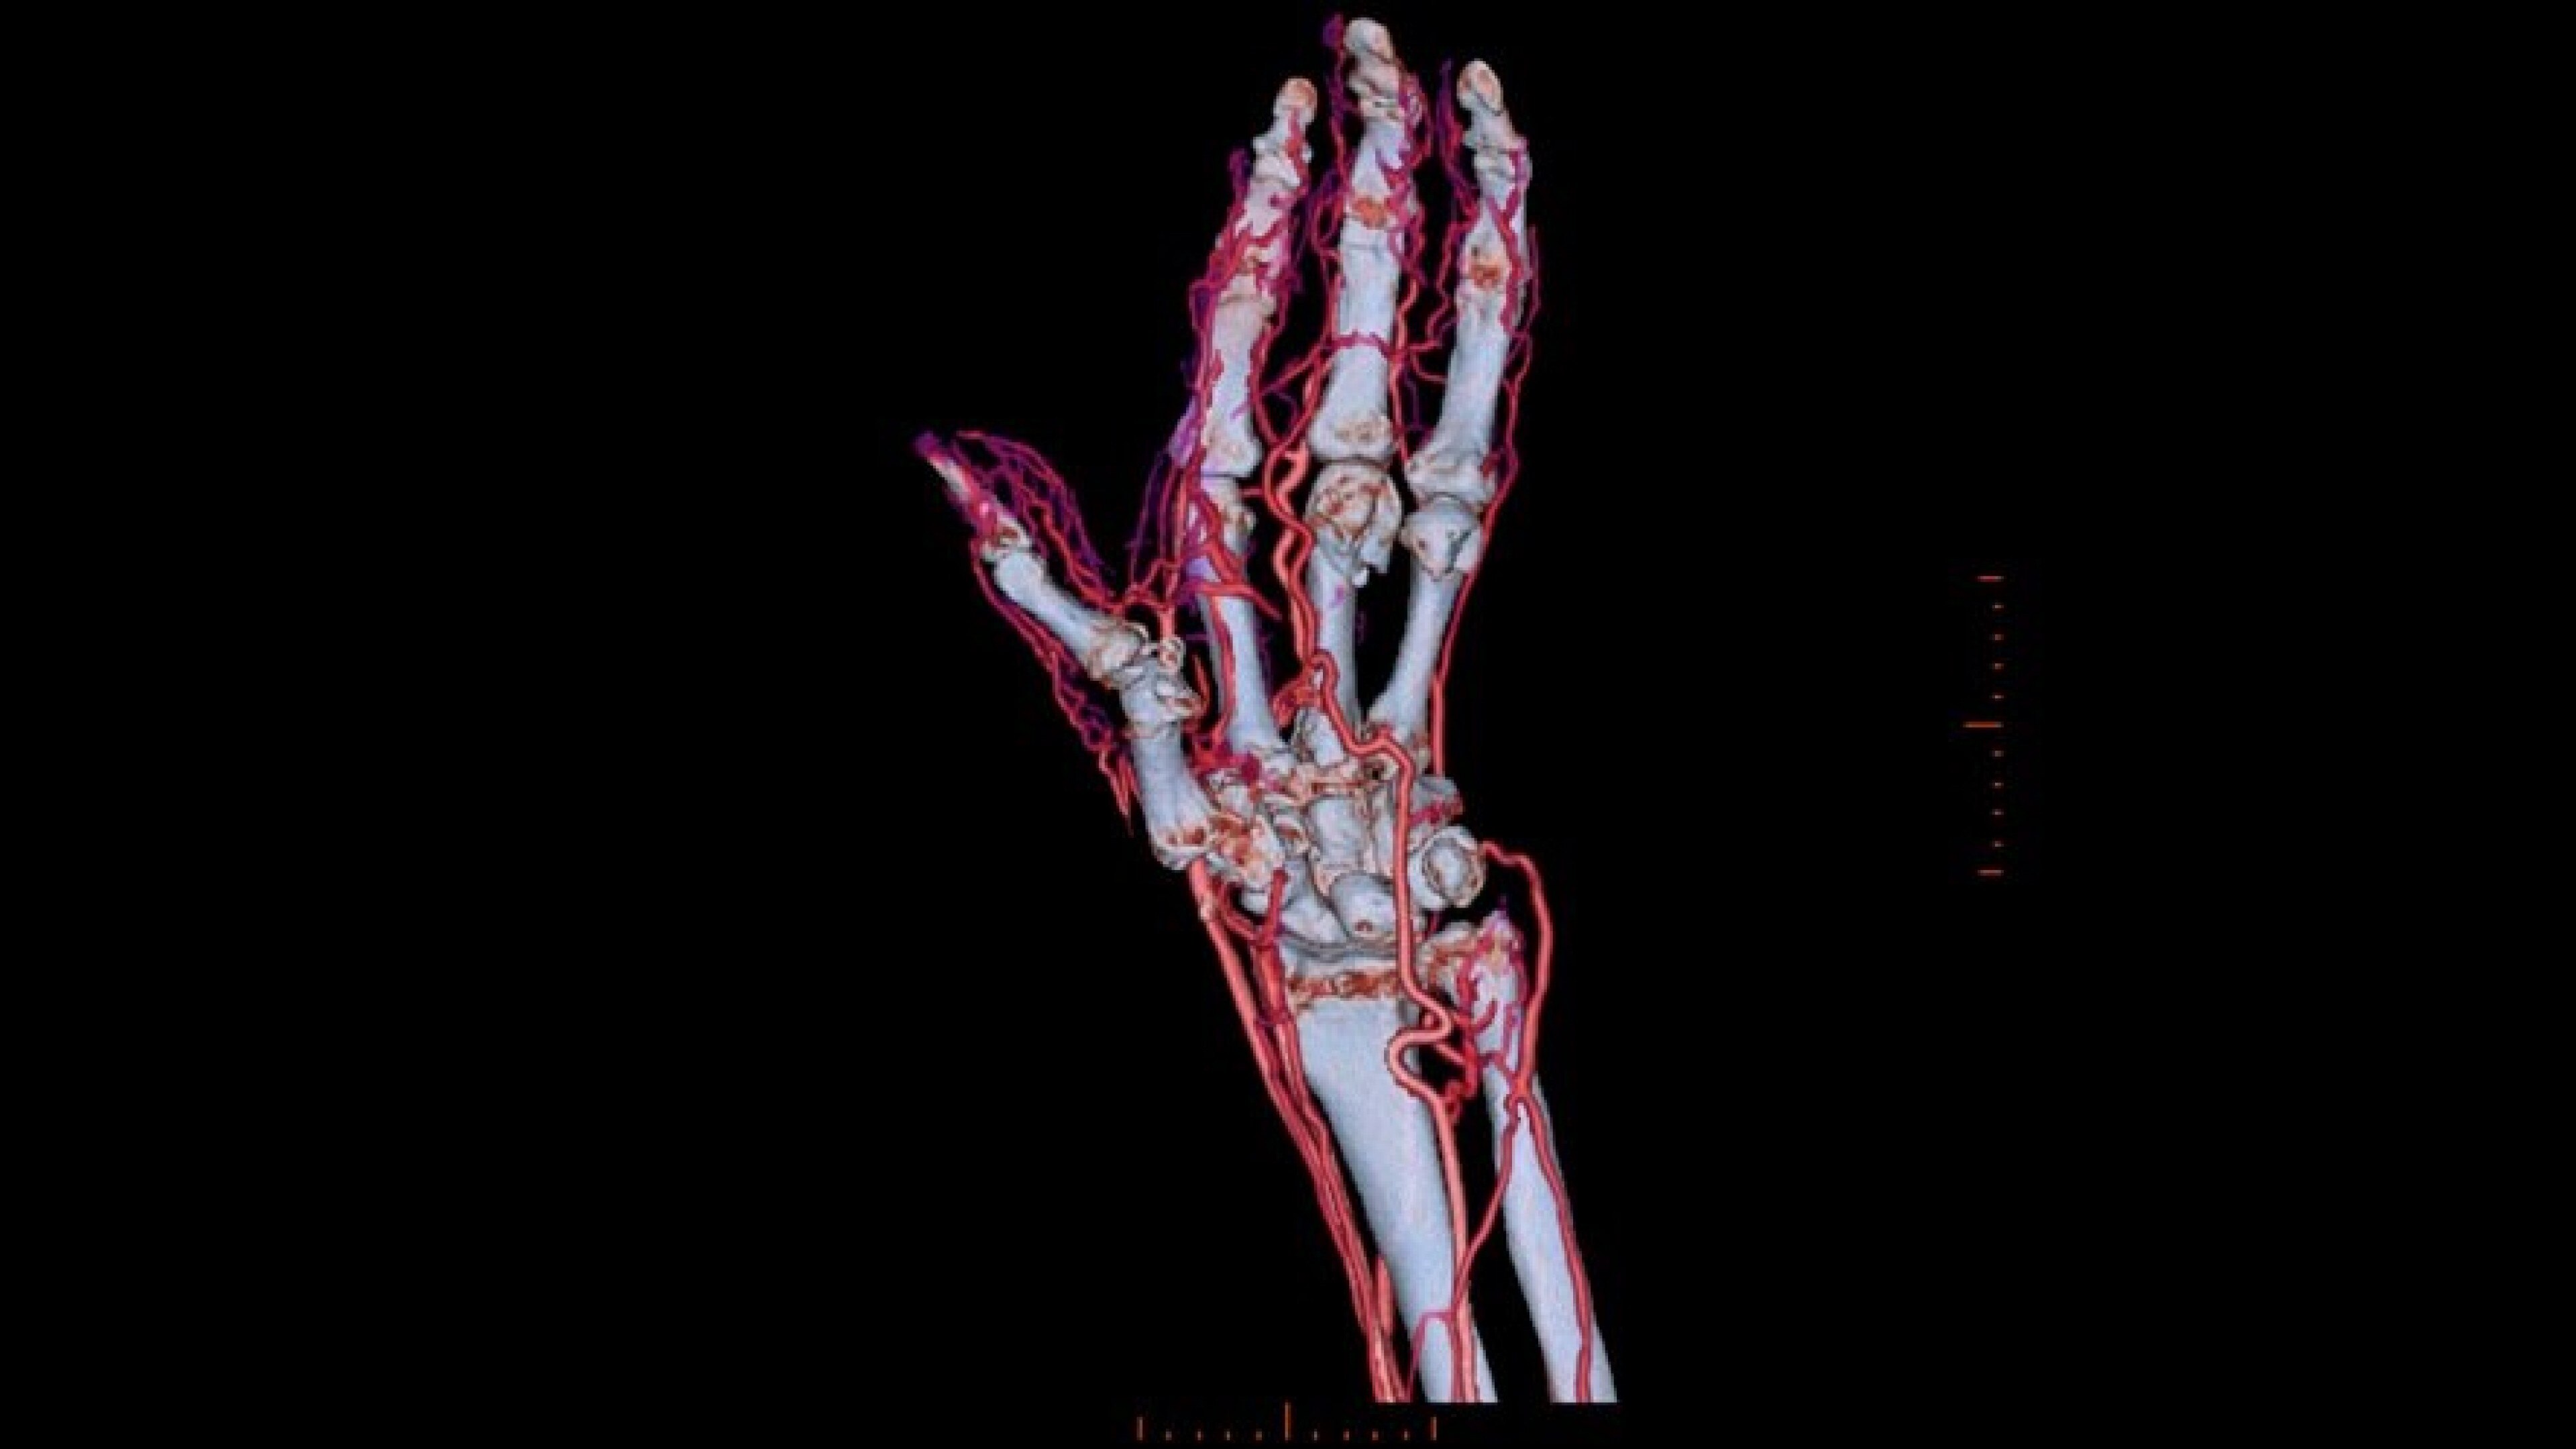

Autobone & VesselIQ Xpress

Fast and efficient vessel analysis from CT Angiography exams.

• Automated real-time fast tracking for all vasculature.

• Perform vessel analysis from any 3D or reformatted image with one or two clicks.